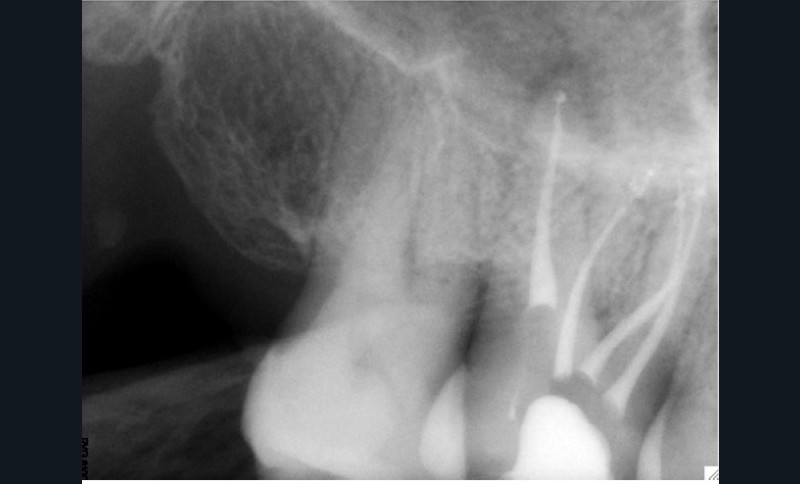

Si les isthmes sont particulièrement mis en évidence au niveau des molaires mandibulaires, cela devient médicalement important au niveau des molaires maxillaires.

La diffusion bactérienne et de leurs toxines, au niveau des molaires maxillaires est à l’origine d’un grand nombre de sinusites maxillaires chroniques, d’origine dentaire. Celles-ci sont principalement causées par l’absence de traitement du deuxième canal MV, qui existe dans 90 % des cas, et il est à noter que ces deux canaux – MV1 et MV2 – sont également reliés par un isthme.

Le nettoyage des isthmes intercanalaires reste un réel problème, et semble responsable de nombreux échecs [43]. Par ailleurs, il est nécessaire d’utiliser des instruments qui évitent de propulser les débris, tant apicalement que latéralement, en obturant les entrées isthmiques avec des débris compactés.

L’utilisation d’instruments en nickel titane, tels que le XP Shaper (FKG), le Vortex blue (Dentsply) ou le Profile (Dentsply), optimise la remontée des débris et s’inscrit dans cette nouvelle philosophie. En conséquence, la combinaison XP Shaper, XP Finisher et l’irrigation avec l’Er:YAG semblent optimiser nos traitements [44,45].

Le passage du laser est répété plusieurs fois, en début, au milieu et en fin de préparation. Un protocole peut alors être proposé : 40 mJ ; 20 Hz (fig. 7). L’utilisation de biocéramiques Bioroot (Septodont) ou Total Fill R (FKG) permet de sceller le système ainsi nettoyé, en assurant une action biologique de longue durée [46] (fig. 8a à c).